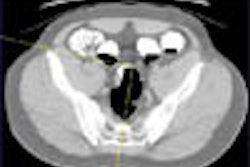

Digital image review is required for VC, and you might get by with cine axial review. But without 3-D for problem solving, there will be times when it's impossible to distinguish a fold from a polyp, Barish said.

The optimal workstation will give you simultaneous prone and supine imaging, fully integrated 2-D and 3-D, and perhaps a third "novel" viewing mode. You could also think about structured reporting, computer-aided detection (CAD), and integration with a RIS attached to a database that could handle follow-up, like in mammography.